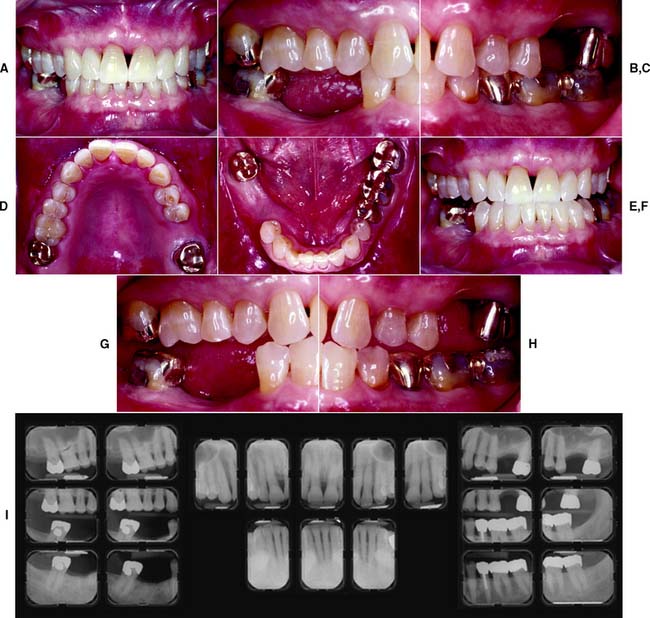

This class (Figs. 1-31 and 1-32) is characterized by substantially compromised location and extent of edentulous areas in both arches, abutment condition necessitating substantial localized adjunctive therapy, occlusal characteristics necessitating reestablishment of the entire occlusion without a change in the occlusal vertical dimension, and residual ridge conditions.

Fig. 1-31 Class III patient. This patient is categorized as Class III because the edentulous areas are located in both arches and there are multiple such locations within each arch. The abutment condition is substantially compromised as a result of the need for extracoronal restorations. There are teeth that are extruded and malpositioned. The occlusion is substantially compromised because reestablishment of the occlusal scheme is required without a change in the occlusal vertical dimension. A, Frontal view, maximum intercuspation. B, Right lateral view, maximum intercuspation. C, Left lateral view, maximum intercuspation. D, Occlusal view, maxillary arch. E, Occlusal view, mandibular arch. F, Frontal view, protrusive relationship. G, Right lateral view, right working movement. H, Left lateral view, left working movement. I, Full-mouth radiographic series.

(From McGarry TJ, et al: Classification system for partial edentulism. J Prosthodont 11:181, 2002.)

Fig. 1-32 Class III patient. The patient is categorized as Class III because large defective amalgam and composite restorations are present in four sextants. The remaining tooth structure is substantially compromised in most posterior teeth. The occlusion is substantially compromised, necessitating reestablishment of the occlusal scheme without a change in the occlusal vertical dimension. A, Frontal view, maximum intercuspation. B, Right lateral view, maximum intercuspation. C, Left lateral view, maximum intercuspation. D, Occlusal view, maxillary arch. E, Occlusal view, mandibular arch. F, Panoramic radiograph.

(From McGarry TJ, et al: Classification system for the completely dentate patient. J Prosthodont 13:73, 2004.)